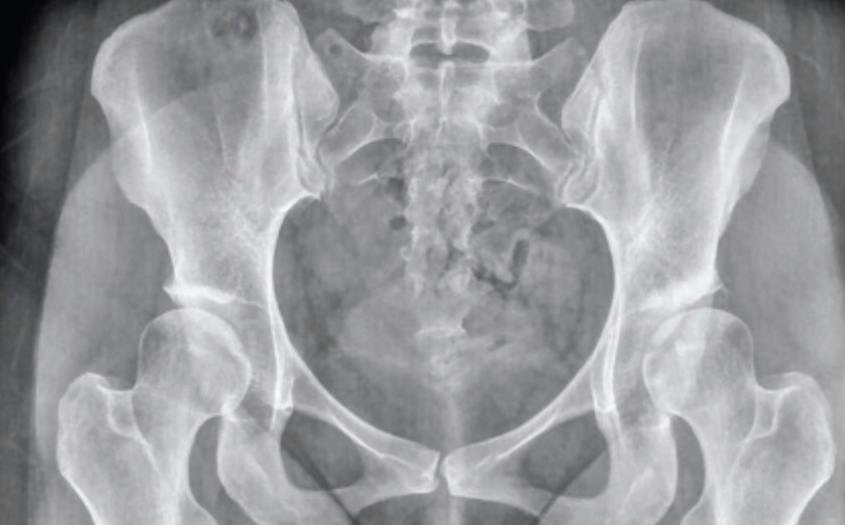

Displazik kalça zemininde gelişen artrozu gösteren röntgen filmi